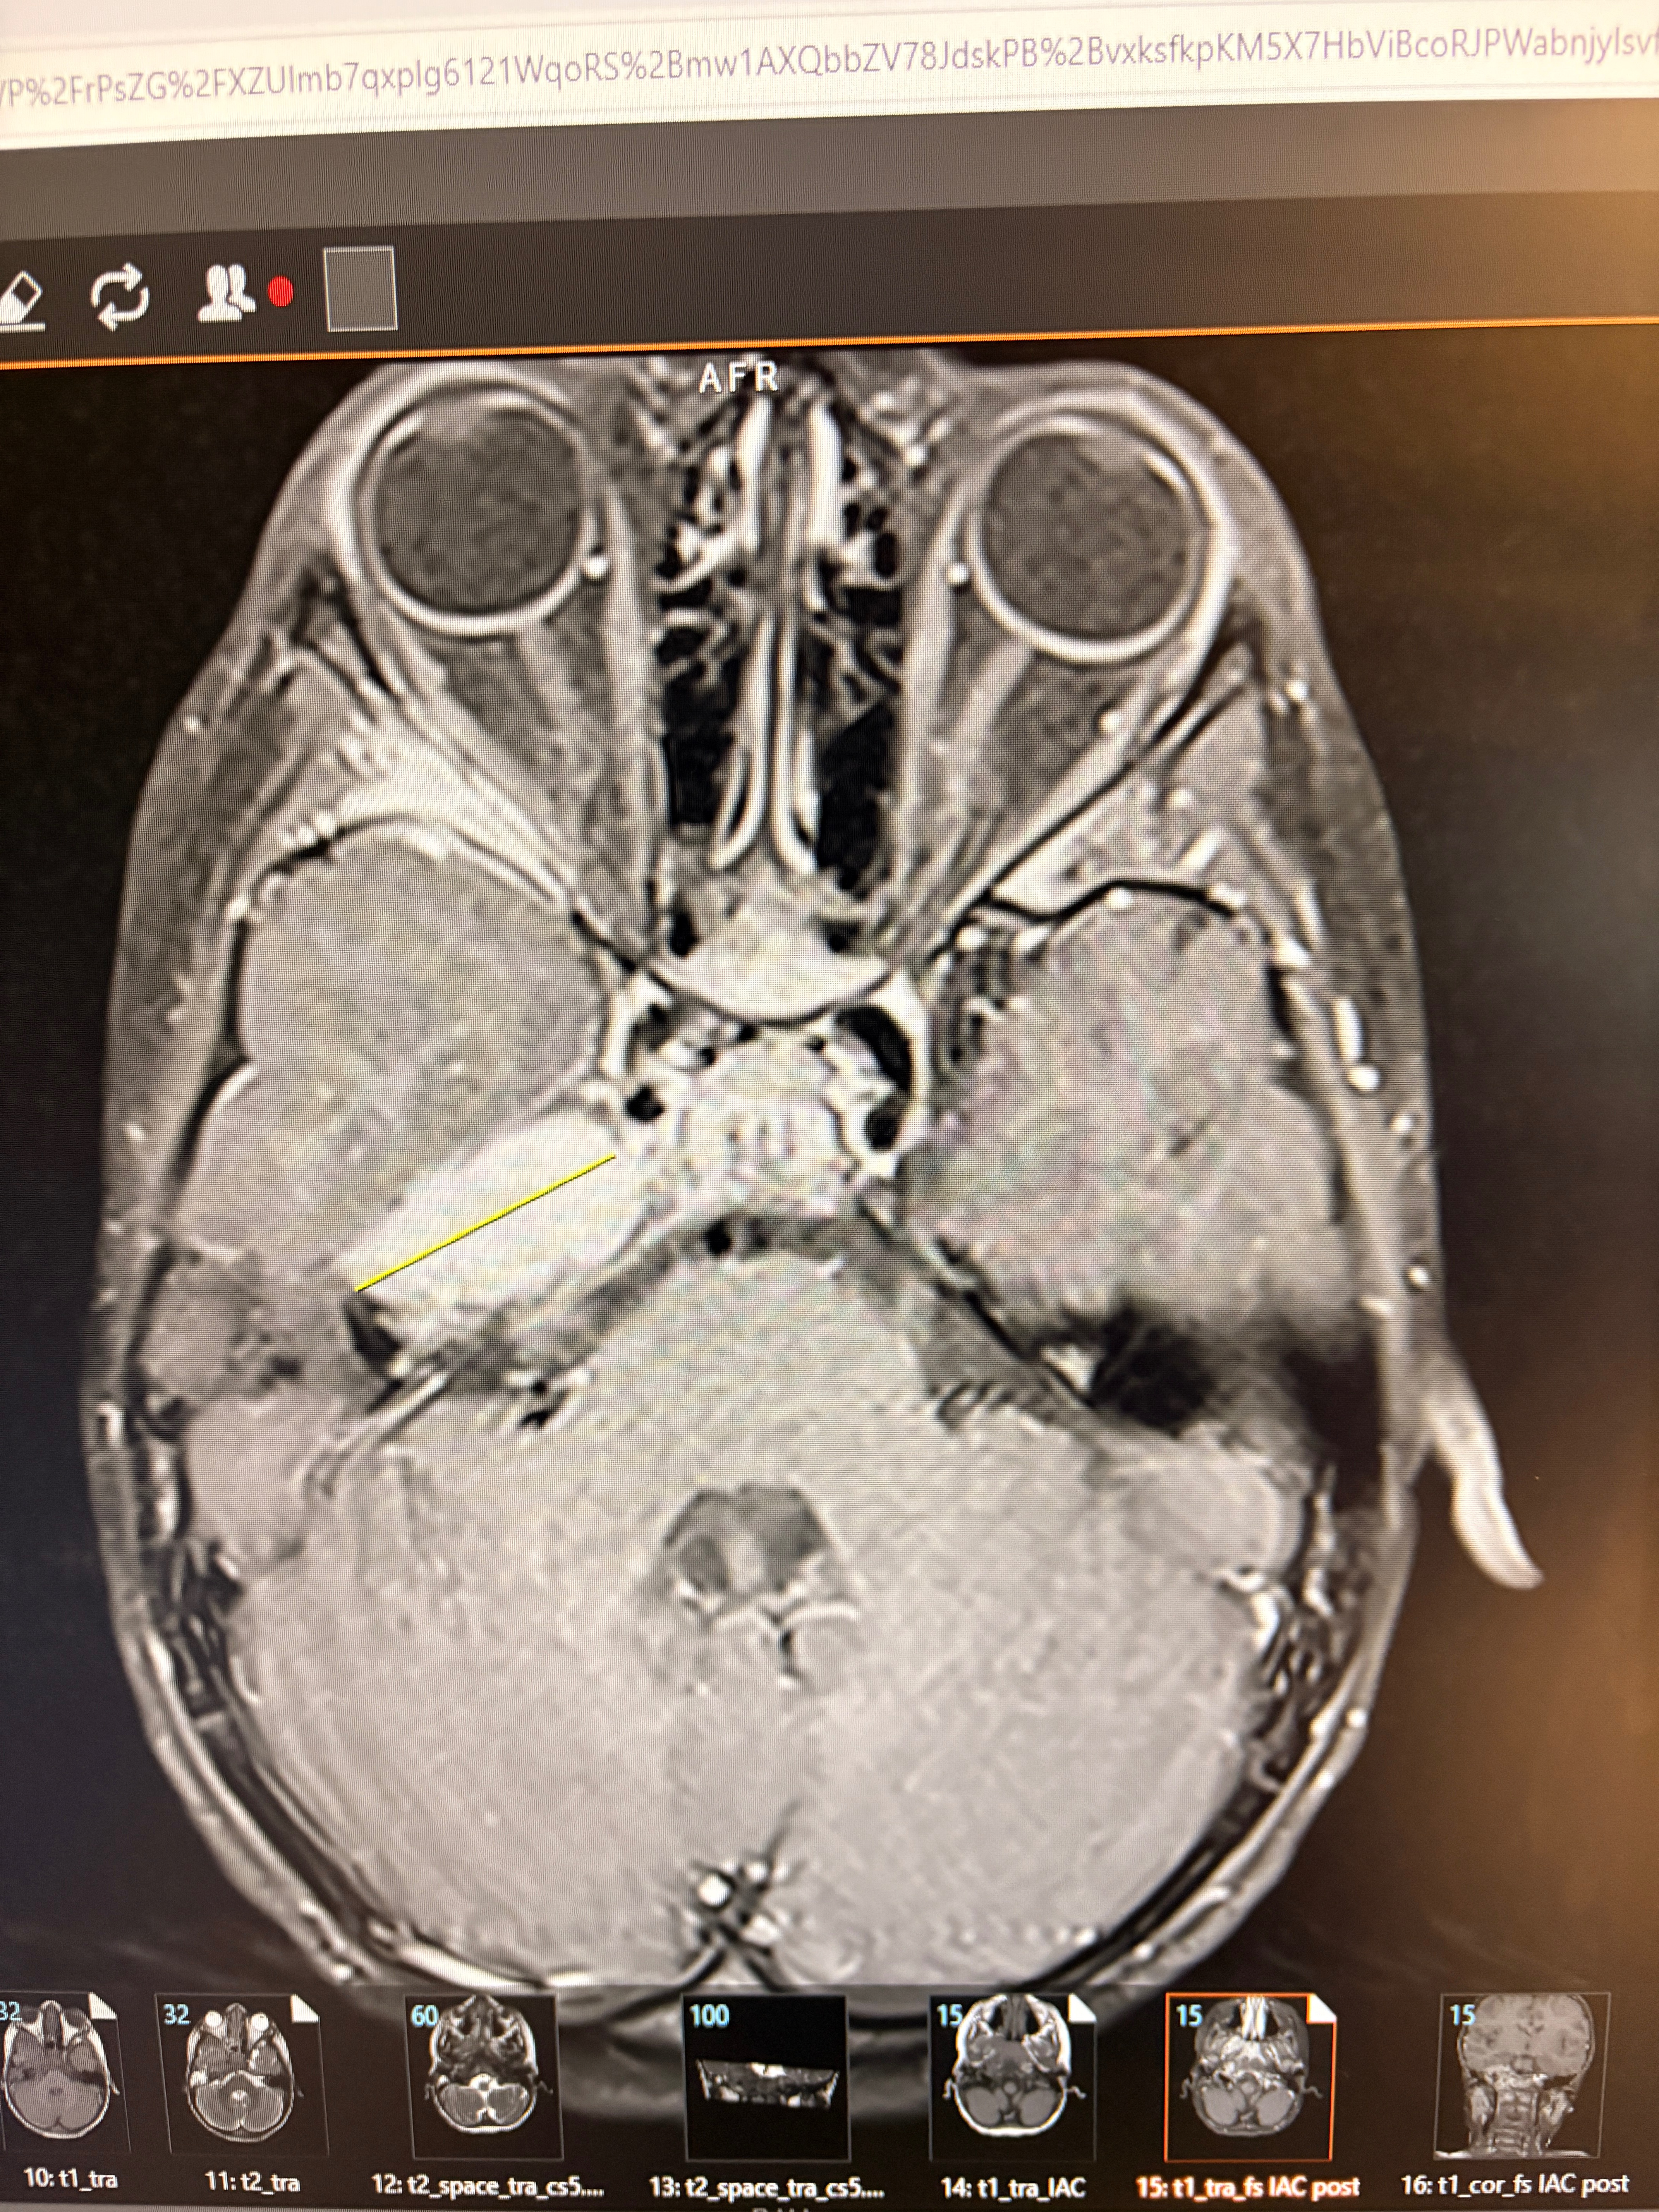

My name is Mishawn, and I’m a mother fighting for my son, Zamari. Recently, our lives changed overnight. What started as an emergency room visit turned into something far more serious. Doctors discovered a tumor near Zamari’s brain, along with additional lesions on his spine and hip. Right now, we are still waiting for a full diagnosis, and every day feels like a mix of fear, uncertainty, and hope. Zamari is only 3 years old. He is strong, loving, and full of light—even in the middle of hospital visits, testing, and everything his little body is going through. As his mother, I’ve made it my mission to be his voice, his advocate, and his comfort through it all.